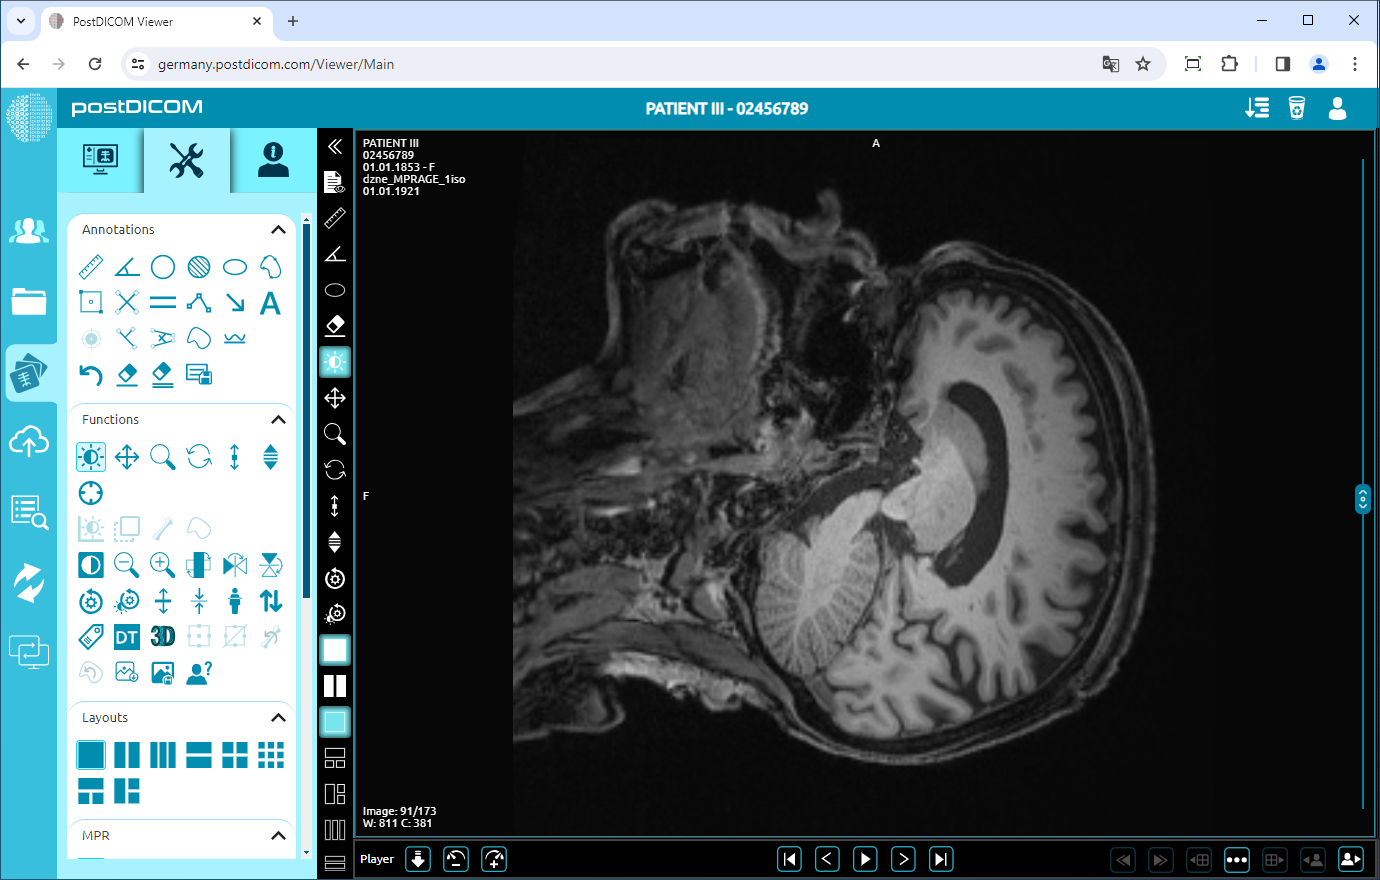

Rotate

Click on the “Rotate 90 Degrees” icon on the left side of the page.

If you click once, the image will rotate 90 degrees to the right. You can click twice to rotate the image 180 degrees, three times click to rotate it 270 degrees or four times click to rotate it 360 degrees (return to the original plane). The image rotated 90 degrees is shown below.